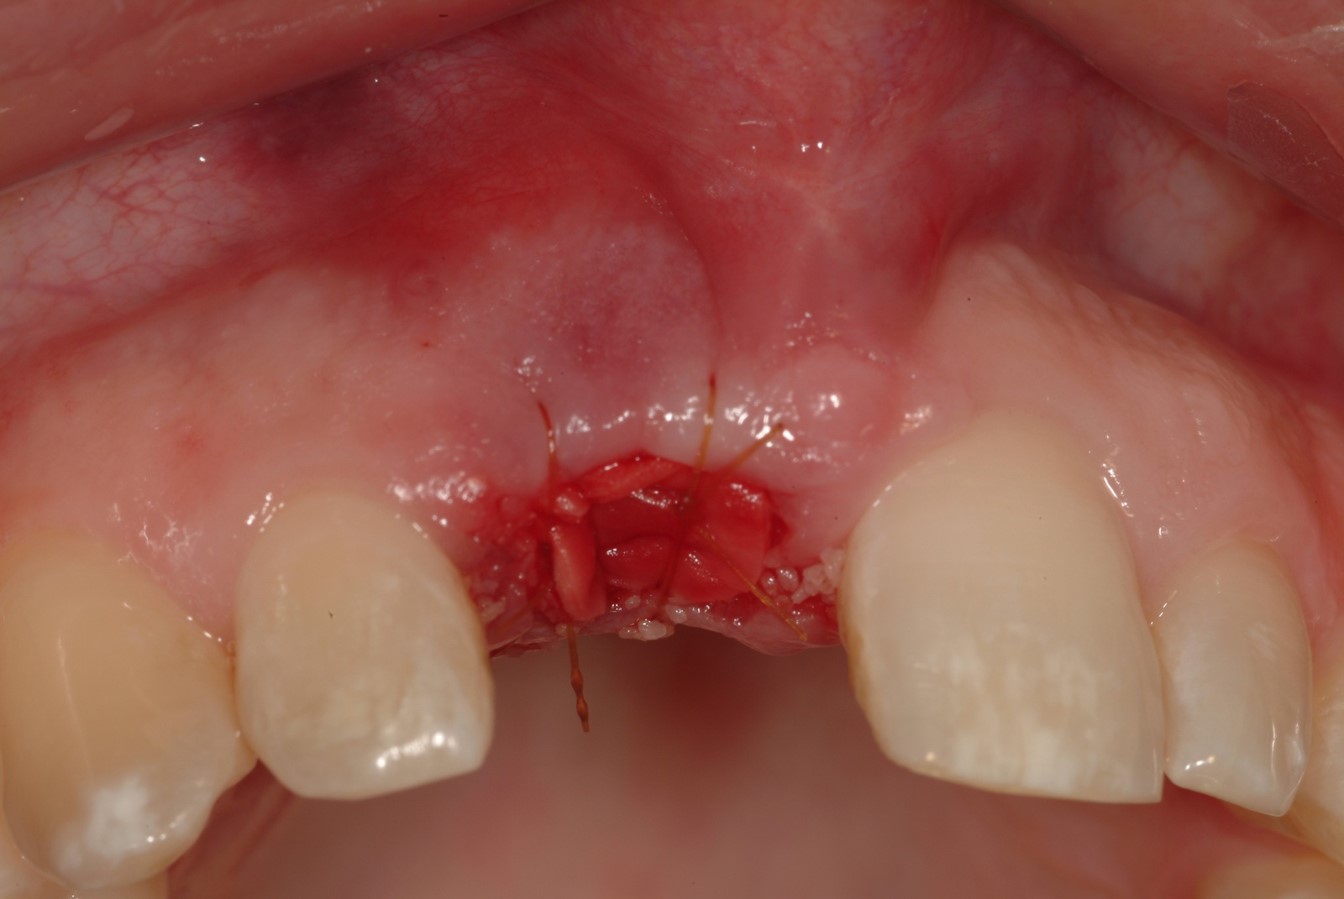

Fig 15. A tunneling procedure with a small connective tissue graft was performed to establish extra soft tissue with a thickened biotype.

Figure 15

Fig 16. Close-up view of the patient’s gingival architecture following tissue graft healing.

Figure 16

However, by giving consideration to the most appropriate and minimally invasive sequence of care, this led to performing predictable procedures beginning with a tunneling procedure with a small connective tissue graft (Figure 15). Once the connective tissue graft healed (Figure 16), extra soft tissue with a thickened biotype was available. This would enable minimally invasive extraction using piezosurgery—without damaging the soft tissues (Figure 17)—followed by immediate implant placement according to 3D implant treatment planning (Figure 18 through Figure 20).